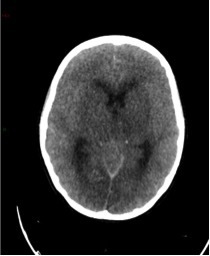

Un scanner cérébral sans injection est réalisé. Les reformations axiales vous sont présentées.

Question 10 : Ce scanner présente :

Les espaces sous sous-arachnoidiens ne sont plus visibles. Ne pas confondre la substance grise qui arrive au contact des os du crâne, avec une hyperdensité spontanée méningée.

Le volume des ventricules paraît faussement augmenté du fait de l’effacement diffus des sillons corticaux.

Qui traduit une augmentation du volume cérébral.

Aucun des deux hémisphères cérébraux ne passe sous la faux du cerveau. L’augmentation du volume cérébral est diffuse.

Effacement diffus des sillons corticaux avec début de dédifférenciation des de la substance blanche - substance grise notamment des noyaux centraux. Cela traduit un œdème cérébral diffus secondaire à un bas débit cérébral.